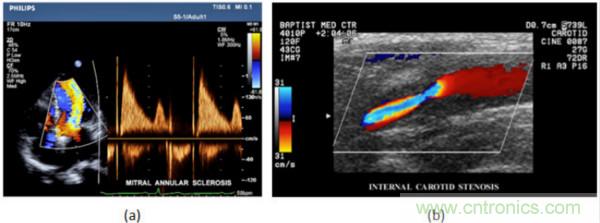

在CW和PW多普勒模式中,流信息是從一個聚焦聲束中獲得的,類似於A模式成像。在20世紀80年代,研究人員基於彩色多普勒技術完成了血流分布的二維信息可視化。彩色多普勒處理也是基於B模式/PW模式信號路徑。從感興趣區域收集多幀RF數據。由於感興趣區域中的血液流動導致圖像幀之間存在數據差異。相域中的自相關和時域中的互相關兩種算法可從RF數據中提取數據方差(即血流速度和方向信息):。genjuyudingyideyansejianbiantiaoxiangyingdiyingshebaokuosuduhefangxiangdexueliuxinxi。tongchang,lansehehongsedaimafenbieshibiechaoxiangheyuanlihuannengqiyidongdexueliu。dangliusuzengjiashishiyonggengliangdeyanse,fanzhiyiran。yanseyingshede2D分布始終疊加在Bmoshituxiangshang,yishishitongshixianshigetijiepoujiegouhexueliu。taduiyuzhenduanxinxueguanjibing,ruxueguanbisaihexinzangbanmofanliu,jiqiyouyong。dianxingdecaiseduopuletuxiangruxiatusuoshi,(b)顯示頸動脈狹窄引起的血流流速變化。

圖7.彩色多普勒成像:(a)以彩色多普勒和CW模式獲得的圖像(由Philips提供); (b)顯示頸動脈狹窄的彩色多普勒(由GE提供)